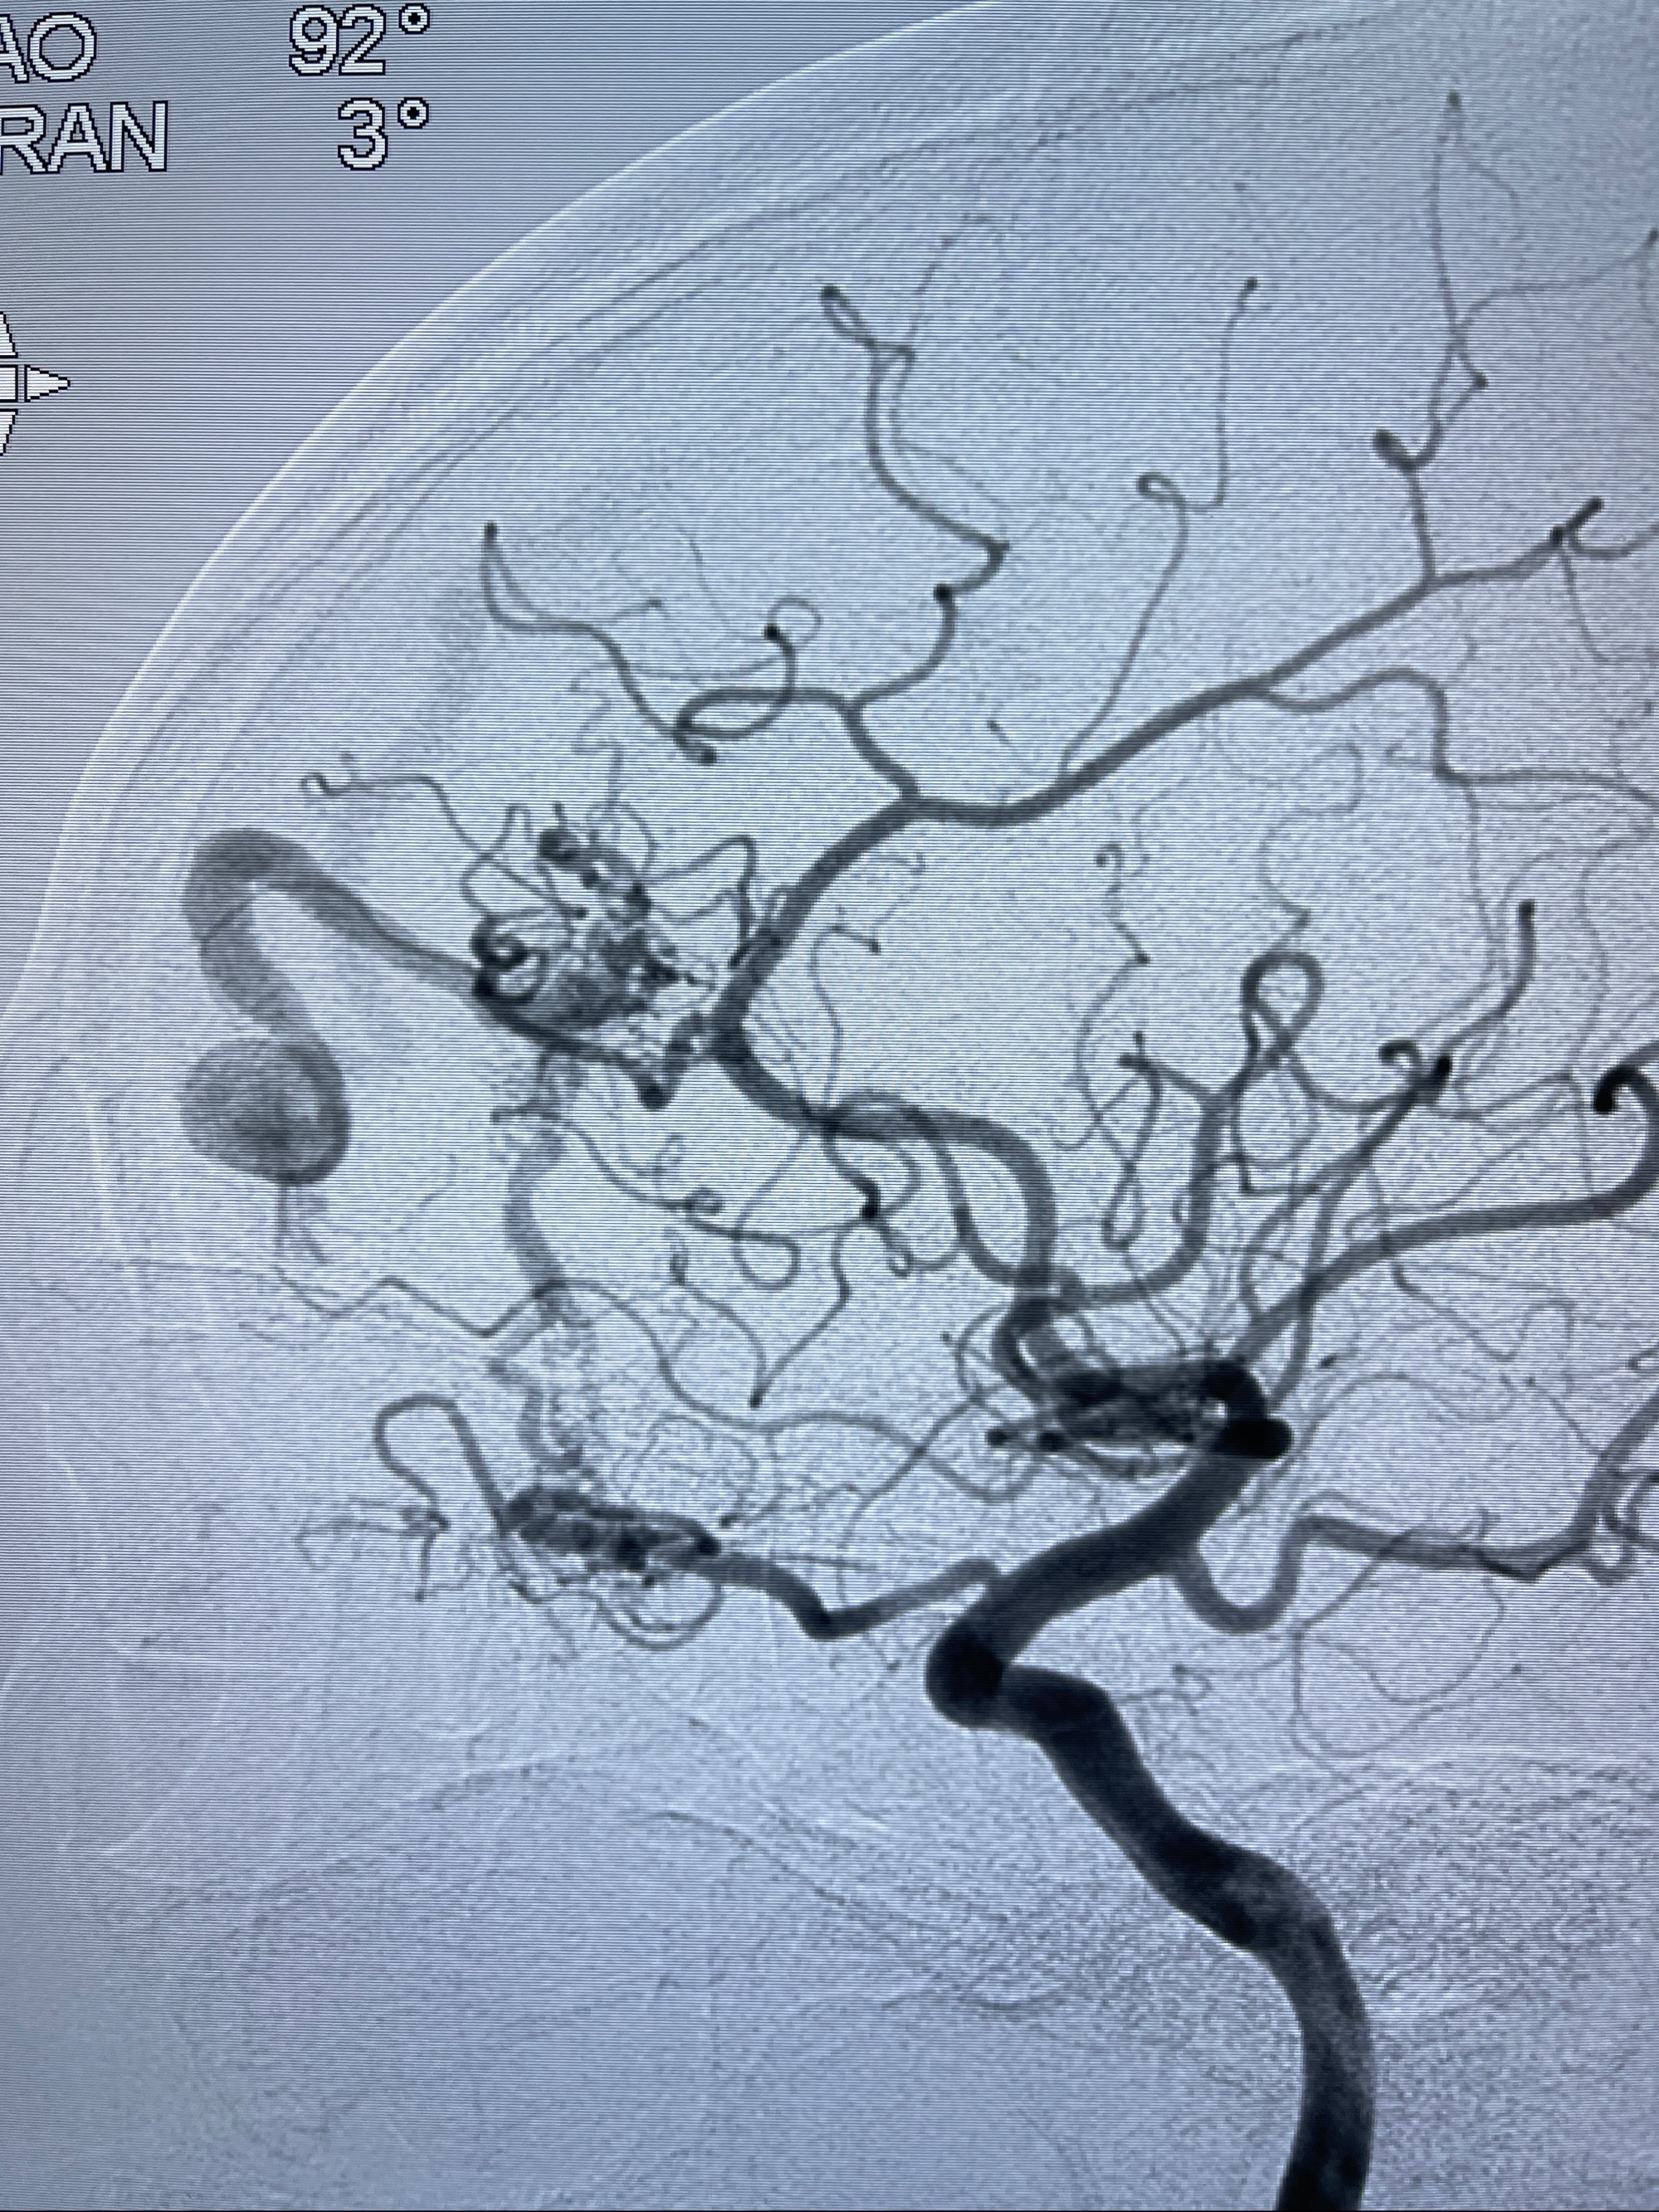

2023年8月21日]景德镇市第一人民医院脑血管造影检查,提示:主动脉弓、双侧颈总动脉、锁骨下动脉造影未见异常,左侧大脑前动脉静脉瘘。

2023-09-13全脑血管造影:前颅底硬脑膜动静脉瘘,供血动脉为双侧胼周动脉、眼动脉脑膜支,静脉向上矢状窦方向引流